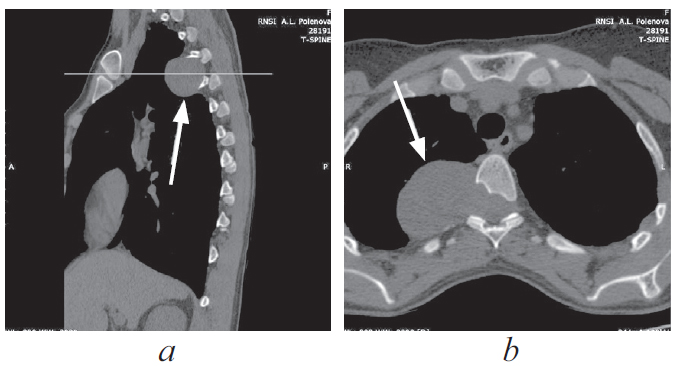

Паравертебральные опухоли медиастинальной локализации — обширная группа патологических процессов с различной гистологической картиной и биологическим поведением, хирургическим лечением при которой занимаются врачи разных специальностей, таких как нейрохирурги и хирурги-онкологи. В настоящее время наиболее предпочтительным методом хирургического лечения данных объемных образований принято считать торакоскопическое удаление, ввиду наименьшей травматичности, меньшего количества осложнений и сокращения времени послеоперационного восстановления пациентов. Представлен клинический случай хирургического лечения пациентки с гигантской паравертебральной опухолью, исходящей из IV грудного корешка. Опухоль стала случайной находкой при выполнении плановой флюорографии. Очаговой неврологической симптоматики не отмечалось. Учитывая топографо-анатомические особенности объемного образования, пациентке было проведено комбинированное двуэтапное оперативное вмешательство: сначала выполняли ламинэктомию и удаление фораминального компонента опухоли из заднего доступа, затем одно портовое видеоассистированное торакоскопическое удаление медиастинально расположенного фрагмента опухоли. Операция проходила в условиях коллабированного легкого на стороне вмешательства. В послеоперационном периоде неврологического дефицита не отмечено, по данным контрольной интроскопии опухоль удалена тотально. По результатам гистологического исследования — нейрофиброма (Grade I). Приведенный клинический пример показывает успешную коллаборацию спинальных и торакальных хирургов, а также иллюстрирует возможности современной минимально инвазивной хирургии.